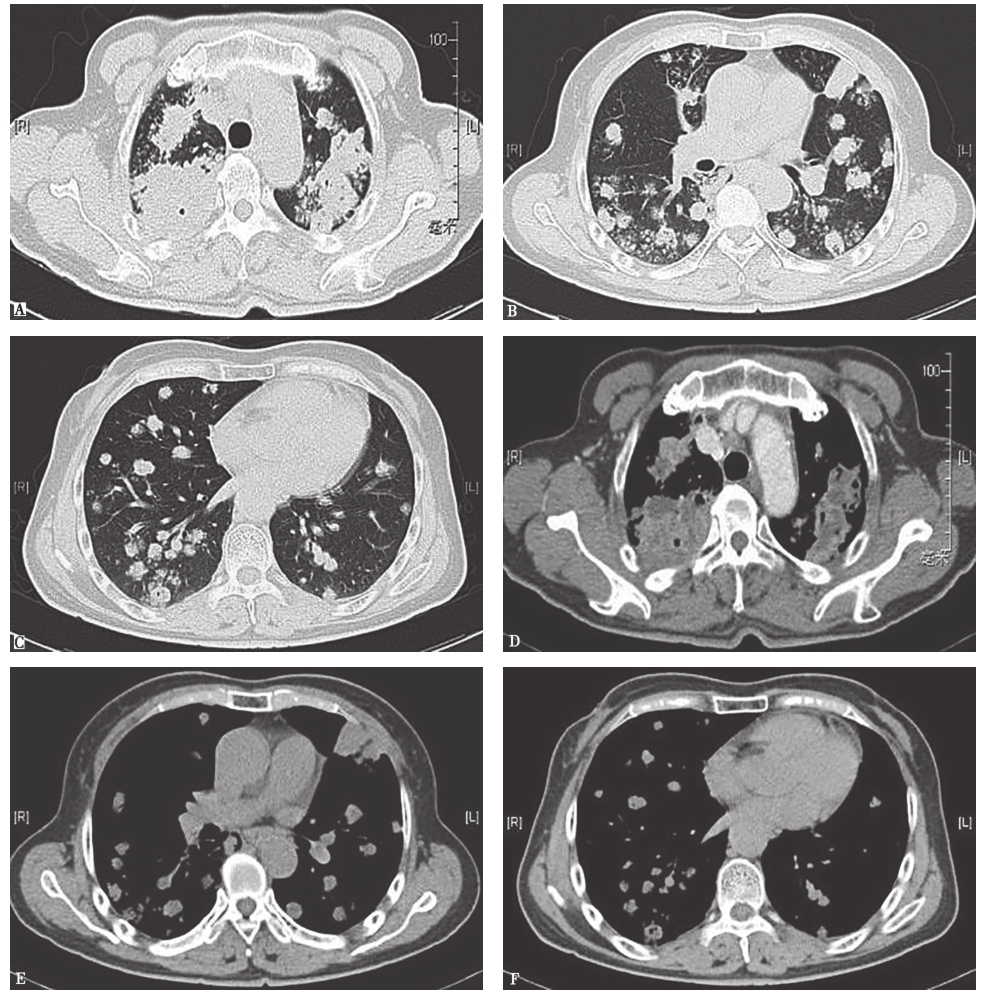

胸部CT平扫和增强扫描示:双肺多发结节及肿块高密度影;纵隔内可见淋巴结轻度增大,无融合趋势(图1)。

图1 胸部CT平扫和增强影像

双肺弥漫多发结节及肿块高密度影(A~F);纵隔内部分淋巴结轻度增大(D~F),无融合趋势